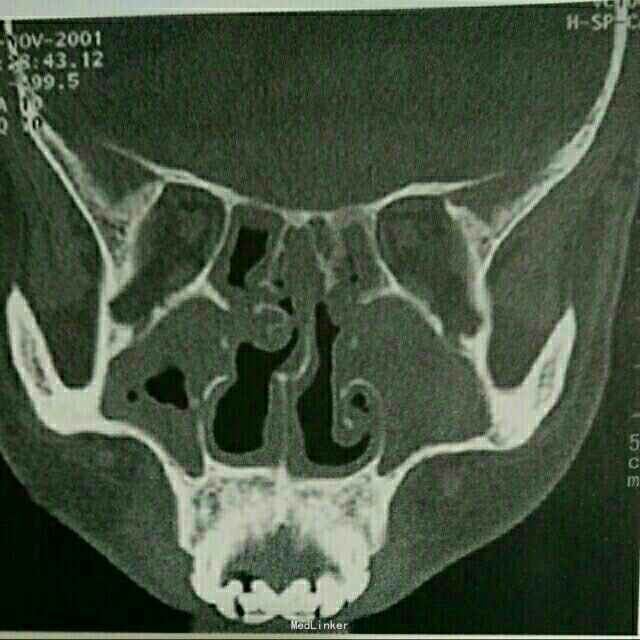

一般生命体征正常,双肺可闻及湿罗音。余未见阳性体征。血常规 正常。尿常规看见镜下血尿。鼻窦CT提示鼻中隔偏曲,双侧筛窦及上颌窦被软组织影充填。取肺组织病理提示间质内小动脉壁纤维素性坏死,中性粒细胞浸润。C-ANCA阳性。

确诊为韦格纳肉芽肿所致的肺部改变。治疗原则按照糖皮质激素加环磷酰胺联合治疗近1年。症状完全缓解,目前已经3年未复发。